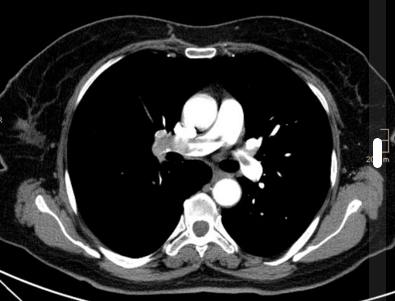

CTPA (spiral CT in arterial phase with a contrast bolus 4ml/sec) is NICE recommended. It has good sensitivity and specificity. It is available 24/7 in all acute hospitals (unlike other possible imaging modalities). Multiplanar reconstructions are very helpful for spotting more subtle PEs. RV > LV diameter on CT is a sign of R heart strain, which SpRs should be able to recognise to aid risk assessment. Image quality is degraded by high BMI (grainy images) and poor contrast (not in phase well so harder to see defect) – 250-300 Hounsfield needed for good diagnosis.

Pulmonary embolism. Case courtesy of Dr Stefan Ludwig, Radiopaedia.org. From the case rID: 13894